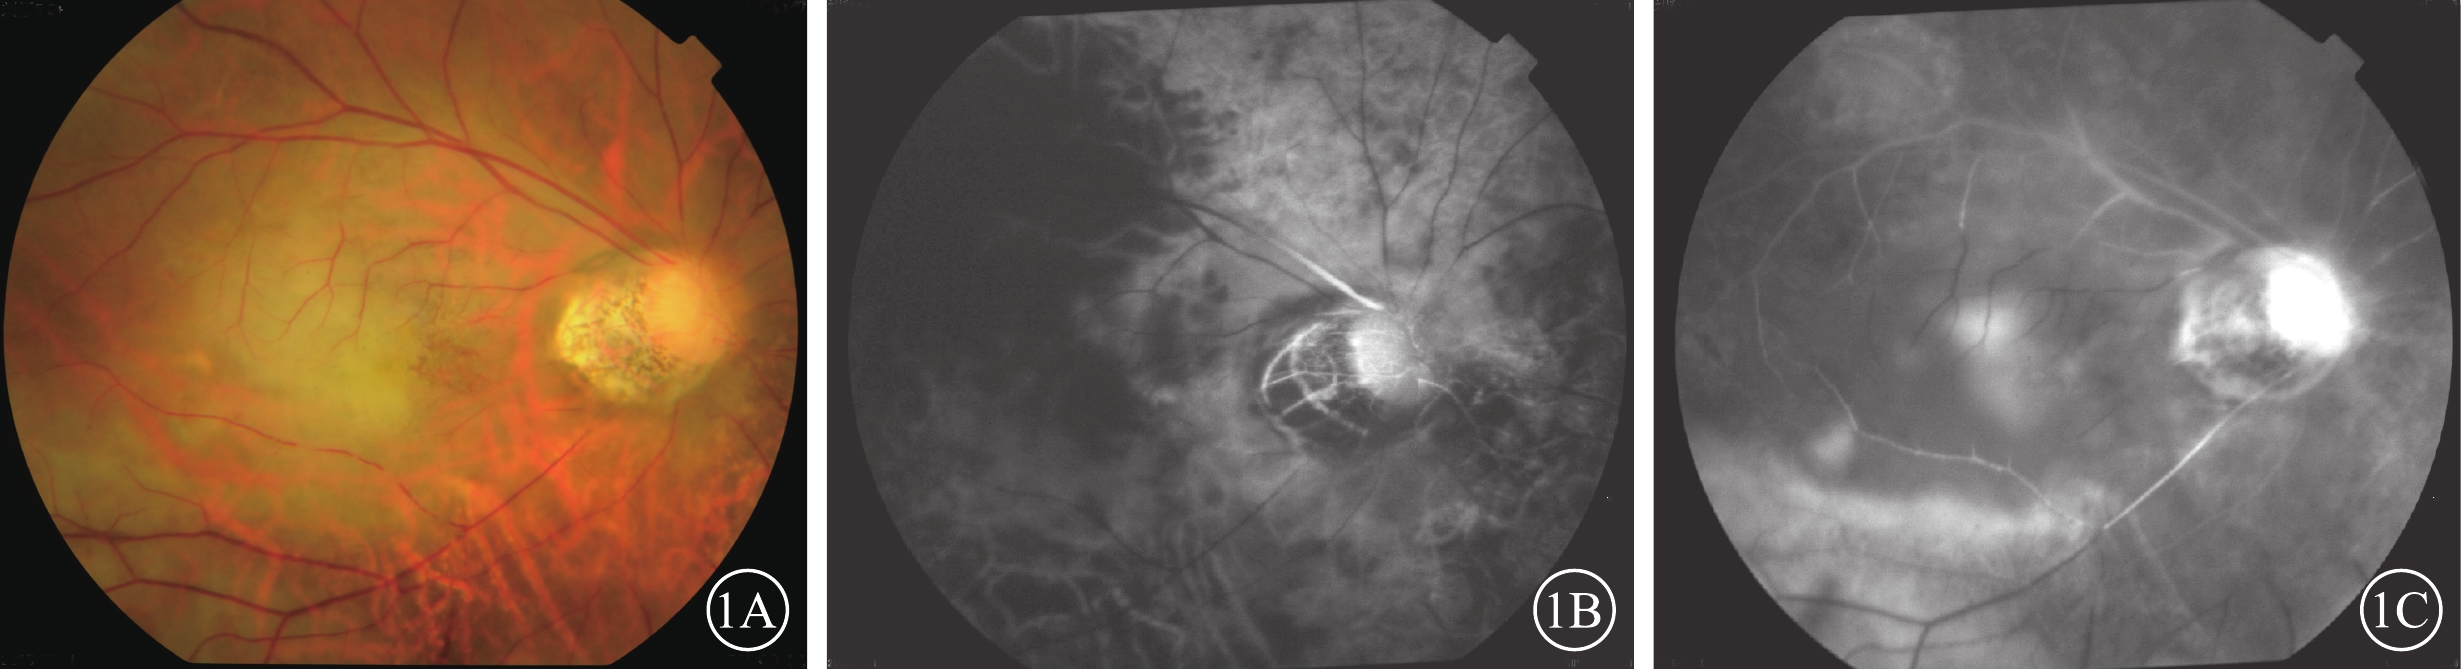

圖1

患眼彩色眼底、FFA像。1A示彩色眼底像,后極部灰白色水腫,黃斑櫻桃紅消失;1B、1C分別示FFA像。1B示臂-視網膜循環時間16.9 s;1C示主干-分支充盈時間11 min 5 s

圖1

患眼彩色眼底、FFA像。1A示彩色眼底像,后極部灰白色水腫,黃斑櫻桃紅消失;1B、1C分別示FFA像。1B示臂-視網膜循環時間16.9 s;1C示主干-分支充盈時間11 min 5 s

患眼視力無光感~0.6。20只眼中,單純OAO 3只眼(15%);OAO合并CAO 4只眼(20%)、MAO 1只眼(5%);單純RAO 7只眼(35%),其中CRAO(圖1)、HRAO、BRAO分別為4、1、2只眼;CRAO伴PCAO 1只眼(5%);PCAO伴NAION 1只眼(5%);CRAO合并DNAO 2只眼(10%);CRAO、PCAO合并右大腦中動脈阻塞1只眼(5%)(表2)。20例中,眼球運動障礙和眼瞼皮膚發紺4例(20%);合并面部疼痛、鼻部皮膚缺血壞死2例(10%)。顱腦CT檢查示右側大腦中動脈供血區域低密度缺血灶1例(20%)。MRA檢查發現顱內新發缺血灶6例(30%)。6例患者中,玻尿酸注射者5例,均為無癥狀的小血管阻塞。自體脂肪注射者1例,男,27歲。右眼視力無光感,眼球運動障礙;左側肢體偏癱。眼底可見后極部灰白色水腫,黃斑中心凹反光消失(圖2A);顱腦CT檢查,右側顳葉低密度梗死灶(圖2B);MRA檢查,右側眼動脈未顯影,大腦中動脈M2段閉塞(圖2C)。

患眼彩色眼底、FFA像。1A示彩色眼底像,后極部灰白色水腫,黃斑櫻桃紅消失;1B、1C分別示FFA像。1B示臂-視網膜循環時間16.9 s;1C示主干-分支充盈時間11 min 5 s

圖1

患眼彩色眼底、FFA像。1A示彩色眼底像,后極部灰白色水腫,黃斑櫻桃紅消失;1B、1C分別示FFA像。1B示臂-視網膜循環時間16.9 s;1C示主干-分支充盈時間11 min 5 s